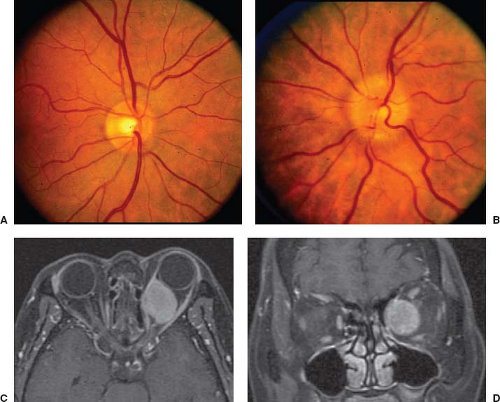

4. 압박성 시신경 병증, Compressive optic neuropathy

안구이후의 시신경이 대뇌의 피질로 연결되는 시각 경로상에,

시각경로의 시신경 섬유다발을 누르고 압박하는 병변이 있는 경우,

압박성 시신경 병증이 발생합니다.

시신경 위축이 양안에서 차이가 저명하게 나고, 환자가 극심한 두통이나, 두통이외의 다른 신경학적인 증상이 있는 경우,

시신경압박성 병변을 의심할수 있습니다.